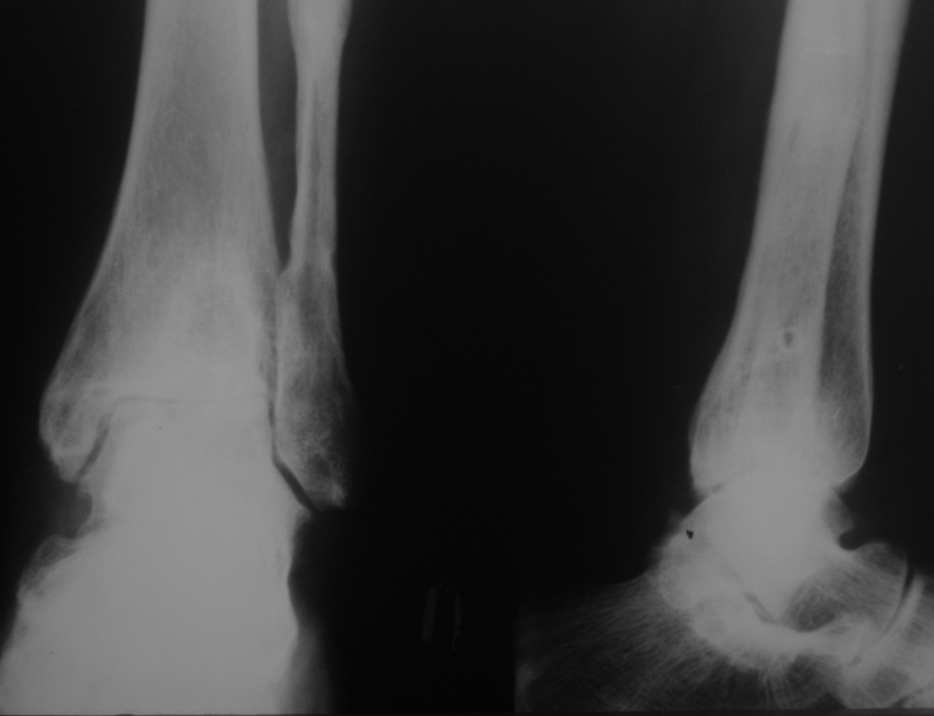

Уважаемые коллеги, разъясните ситуацию.Пациентка, 45лет. 9 месяцев назад произведен синтездвухлодыжечного перелома правой голени.

Конструкции на данный момент удалены. Объем движений на фото. Сейчас беспокоят скованость в области сустава, боли к концу рабочего дня - классическая клиника артроза.Пропила 4 курса найз. Откуда артроз такой выраженности (на рентгенограмме)? Поможет ли консервативное лечение и какое поможет наверняка?

Артроз, во-первых, вследствие неконгруентности суставных поверхностей - имеется укорочение малоберцовой кости; во-вторых имеется синостозирование берцовых костей (вместо тугоэластисчного синдесмоза).

>Артроз, во-первых, вследствие неконгруентности суставных поверхностей - имеется укорочение малоберцовой

Но укорочение - 3мм, и потом суставная поверхность наружной лодыжки не несет осевой нагрузки

>во-вторых имеется синостозирование берцовых костей (вместо тугоэластисчного синдесмоза).

Даже если это были оригинальные имлантаты "Synthes", то к "АО" этот остеосинтез не имеет ни какого отношения. Потому, что вся философия АО в отношении переломов лодыжек основана на том, что наружная лодыжка это нагружаемая часть сустава, на которую приходится примерно 1\6 веса тела. Восстановление длины м\б кости является приоритетным, и наружную лодыжку называют ключом г\ст сустава.

"Стягивающий винт на синдесмоз" противоречит АО, т.к. этот винт должен быть позиционным и не должен создавать компрессиию на уровне сочленения берцовых костей и между наружной лодыжкой и таранной костью. Стягивающий винт - основная причина синостоза на месте синдесмоза.

этих-то 3 мм и достаточно для формирования артроза. Наружная лодыжка - ключ к голеностопному суставу!